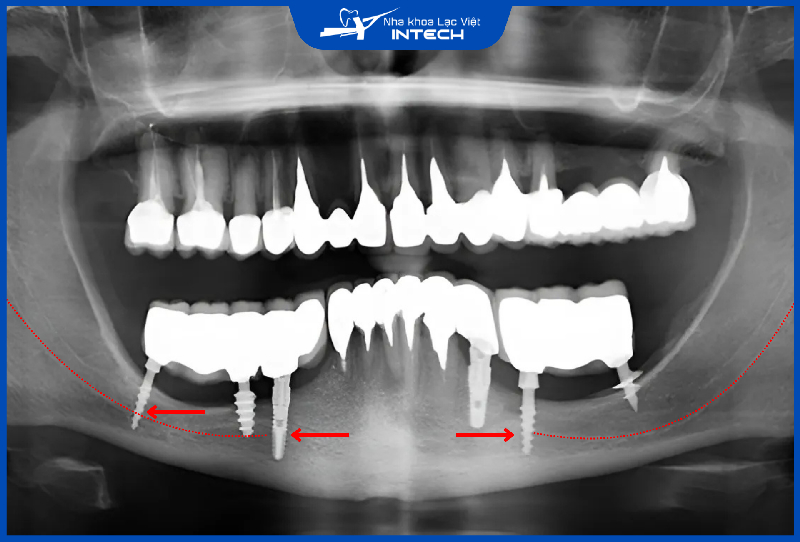

2.3. Trụ Implant không tích hợp vào xương hàm

Trong trường hợp trụ Implant không tích hợp vào xương hàm, răng Implant trở nên lỏng lẻo, không thể chịu được lực nhai, đau nhức, sưng viêm và thậm chí có nguy cơ bị đào thải. Nếu không được xử lý kịp thời, các biến chứng này có thể dẫn đến tiêu xương hàm, mất thêm răng hoặc mất răng toàn hàm, làm phức tạp việc điều trị về sau.

Nguyên nhân khiến trụ Implant không tích hợp tốt vào xương hàm thường đến từ hai yếu tố chính.

• Vật liệu cấy ghép chất lượng kém: Mất tích hợp xương có thể xảy ra do chân Implant không được xử lý bề mặt tốt, lỏng vít kết nối trụ phục hình và chân Implant hoặc do lỏng kết nối răng sứ và trụ phục hình. Để ngăn ngừa, cô chú/anh chị cần lựa chọn cả 3 bộ phận bao gồm: trụ Implant, trụ phục hình và mão răng sứ đều có chất lượng cao.

• Tay nghề bác sĩ và kế hoạch điều trị không tốt: Kỹ thuật đặt trụ sai lệch, không đánh giá đúng tình trạng xương hàm hoặc không xử lý các vấn đề bệnh lý miệng trước khi phẫu thuật không chỉ làm tăng nguy cơ thất bại mà còn kéo dài thời gian điều trị.

Cô chú/anh chị có thể nhận biết trụ Implant không tích hợp vào xương qua các dấu hiệu rõ rệt sau khoảng 3 – 6 tháng sau cấy ghép. Các triệu chứng bao gồm trụ Implant lỏng lẻo, cảm giác đau nhức kéo dài không giảm và xuất hiện viêm nhiễm quanh khu vực cấy ghép. Trong trường hợp nghiêm trọng, nướu xung quanh trụ có thể bị sưng đỏ hoặc chảy mủ, cho thấy tình trạng viêm đã tiến triển.

Trụ Implant mất tích hợp có thể do chất lượng trụ không tốt hoặc kỹ thuật cấy ghép không đúng